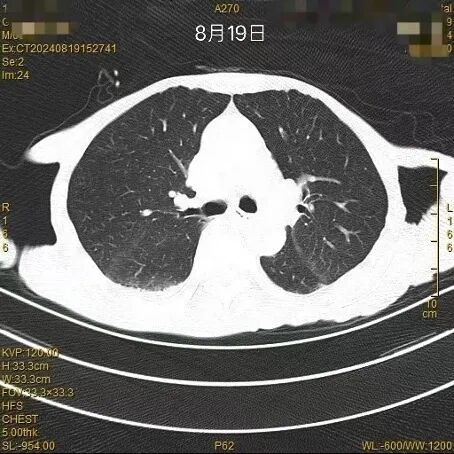

CT影像学检查(7月13日);CT影像学检查(7月16日)

图4-5 胸部CT结果

CT影像学检查(8月19日,较前明显好转)

图6胸部CT结果

对比7月13日、7月16日及8月19日的胸部CT影像(图4-6)可见,经规范抗感染治疗后,患者肺部病灶较前明显吸收好转。